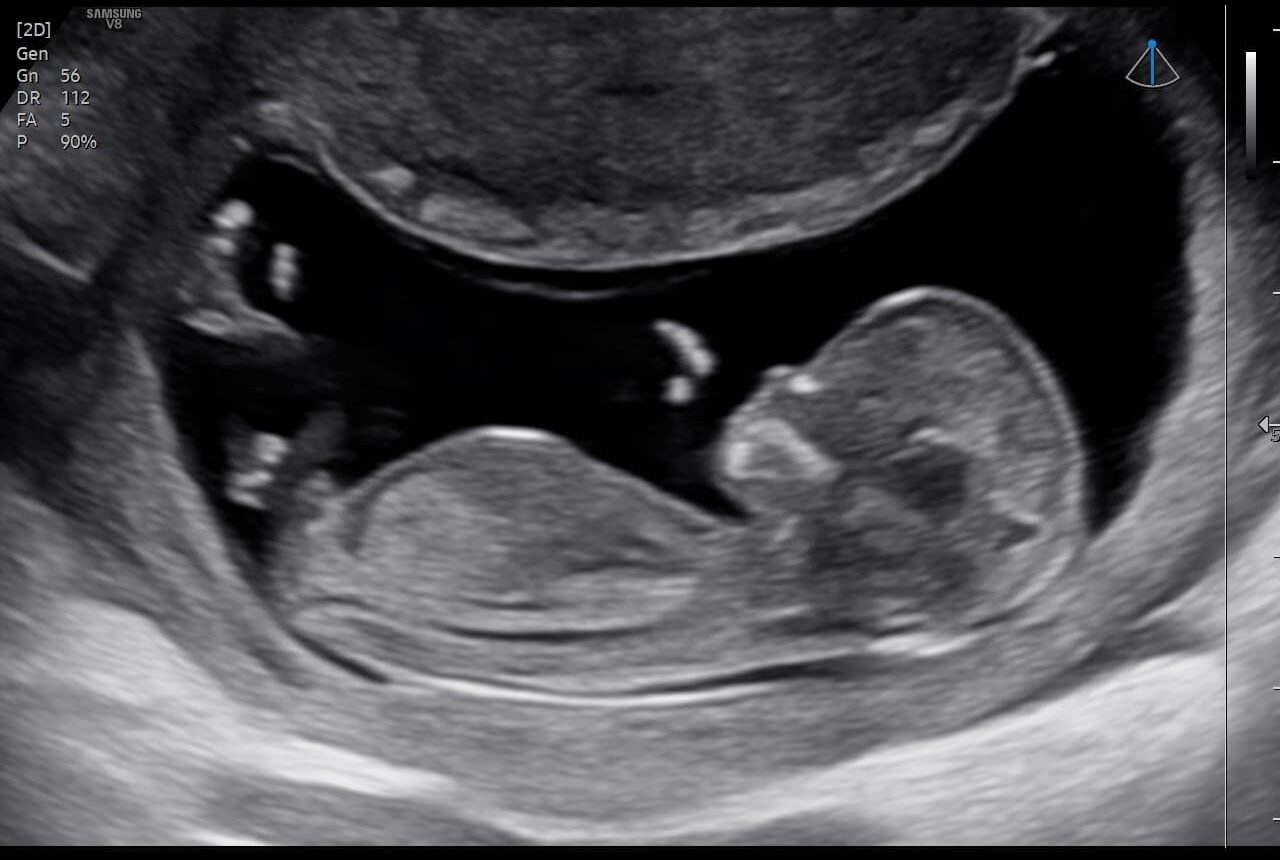

O curso "Morfológico Sem Segredos de 1º Trimestre" tem como objetivo capacitar médicos na realização e interpretação do ultrassom morfológico do primeiro trimestre, seguindo as diretrizes internacionais da ISUOG. Com um conteúdo atualizado e didático, você vai aprender técnicas avançadas para garantir que nenhuma alteração passe despercebida, aumentando sua segurança e precisão nos exames. Ao final do curso, você será capaz de realizar o estudo morfológico com total confiança, interpretando os resultados de maneira assertiva e elaborando laudos completos e detalhados. Tudo isso com a orientação de uma das maiores referências em Medicina Fetal do Brasil, além de ter acesso exclusivo a uma mentoria em grupo para aprofundar ainda mais seus conhecimentos.

- Aula 1: Anatomia Normal no Primeiro Trimestre

- Aula 1: Malformações Detectáveis no Exame de 11 a 14 Semanas